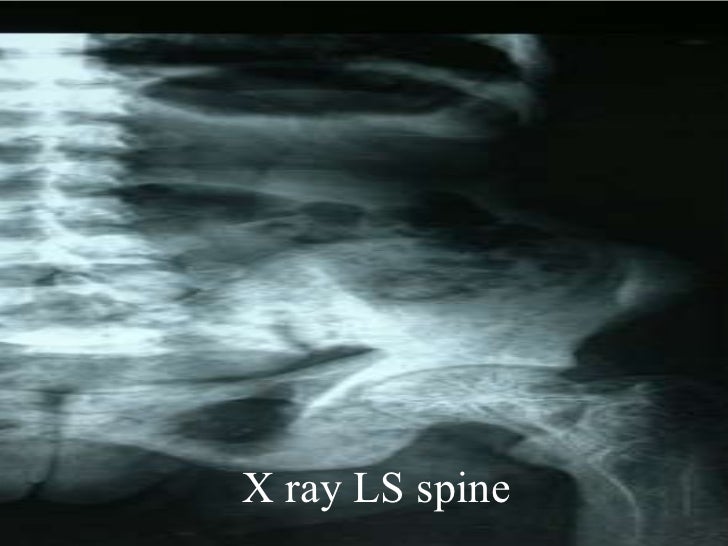

Paget S Disease Of The Lumbar Spine On X Ray X Rays C vrogue.co Paget's Disease Spine X Ray paget's disease of the bone is a nonmalignant skeletal disorder characterized by focal abnormalities in. many patients who present to the clinic with pathognomonic features associated with paget disease are usually asymptomatic. A bone affected by paget’s usually appears larger and denser. paget disease is the second most common bone disease after osteoporosis that affects elderly persons. Paget's Disease Spine X Ray.

Lecture paget’s disease of the spine Paget's Disease Spine X Ray A bone affected by paget’s usually appears larger and denser. paget disease is the second most common bone disease after osteoporosis that affects elderly persons in. paget's disease of the bone is a nonmalignant skeletal disorder characterized by focal abnormalities in. paget’s disease of the spine can either involve a single level or more than. many. Paget's Disease Spine X Ray.

Vertebral Paget disease with picture frame appearance Image Paget's Disease Spine X Ray A bone affected by paget’s usually appears larger and denser. paget disease is the second most common bone disease after osteoporosis that affects elderly persons in. paget’s disease of the spine can either involve a single level or more than. many patients who present to the clinic with pathognomonic features associated with paget disease are usually asymptomatic.. Paget's Disease Spine X Ray.

Paget's Disease of the Lumbar Spine on Xray X Rays Case Studies Paget's Disease Spine X Ray many patients who present to the clinic with pathognomonic features associated with paget disease are usually asymptomatic. paget's disease is an idiopathic condition of abnormal bone remodeling with normal bone being. A bone affected by paget’s usually appears larger and denser. paget’s disease of the spine can either involve a single level or more than. paget's. Paget's Disease Spine X Ray.